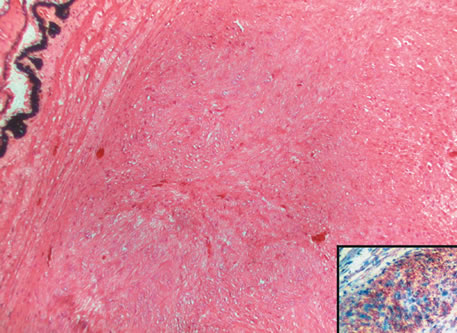

Three histologic patterns of granulomatous inflammation may be seen: diffuse, discrete, and zonal. In diffuse granulomatous inflammation, the epithelioid histiocytes are scattered throughout the involved uveal tissue (Fig. 19). There may be an accompanying background of lymphocytes and plasma cells. Discrete granulomatous inflammation reveals well-circumscribed areas of epithelioid histiocytes (Fig. 20). Zonal granulomatous inflammation consists of a central zone of necrosis and/or polymorphonuclear leukocytes surrounded by epithelioid histiocytes, which is in turn surrounded by a zone of non-granulomatous inflammation consisting of granulation tissue, lymphocytes and plasma cells (Fig. 21).

Fig. 19. Sympathetic ophthalmia. Diffuse granulomatous inflammation involving the choroid. (Hemotoxylin-eosin ×65.)

Fig. 20. Sarcoidosis. Discrete granulomatous inflammation is seen in sarcoidosis. (Hemotoxylin-eosin ×100.)

Fig. 21. Tuberculous choroiditis. A zonal granulomatous inflammation is present. Central area shows necrosis. (Hemotoxylin-eosin ×65.)